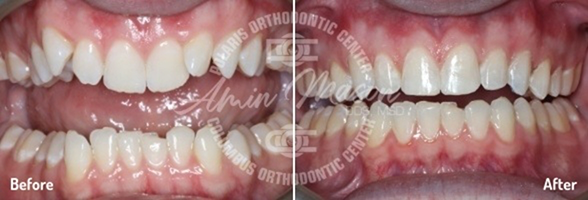

Case 4

This 26-year-old patient wanted to straighten her severely crooked teeth because they made her feel self-conscious. Not wanting to draw any more attention to her teeth, she decided to get Invisalign. Multiple orthodontists told her that her case was too complicated for Invisalign treatment, but she persisted and eventually found Dr. Mason. He was able to combine Invisalign with a class II corrector and elastics to fully address all her issues. After going through the process, she said she was extremely happy with the results and could not stop smiling.